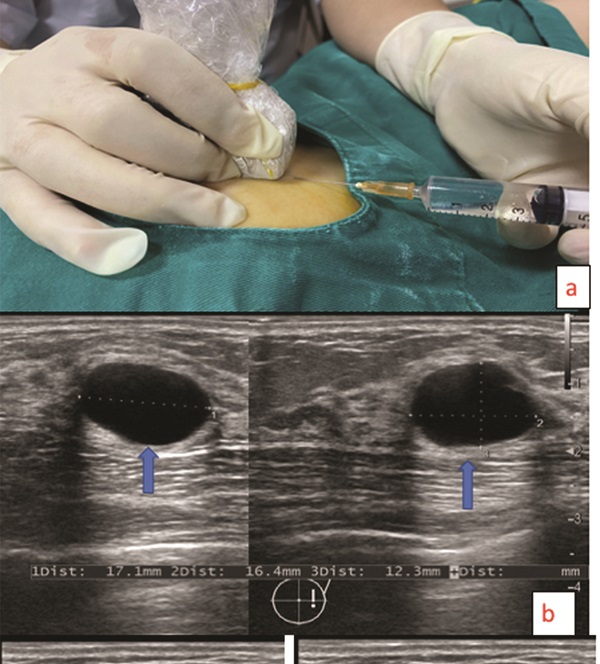

Hiện nay nhiều người đang lựa chọn phương pháp sử dụng kim chọc hút lấy bệnh phẩm tại nang tuyến vú dưới hướng dẫn của siêu âm, sau đó tiêm cồn hoặc chất gây xơ để diệt nang tuyến vú. Đây là phương pháp ít xâm lấn và tỷ lệ tái phát thấp.

Điều trị diệt nang vú bằng các phương pháp can thiệp tối thiểu như tiêm cồn hoặc các chất gây xơ hóa sau chọc hút nang là phương pháp ít xâm lấn và tỷ lệ tái phát thấp. Bên cạnh đó, kỹ thuật này còn giúp diệt chính xác nang cần diệt (nang to, nang nhiễm trùng); diệt được nhiều nang trong một lần; không làm tổn thương nhu mô vú; không để lại sẹo; nhanh chóng thuận lợi, thời gian diệt nang 10 phút; bệnh nhân gần như không cảm thấy đau đớn gì.

Miêu tả quy trình thực hiện kỹ thuật chọc hút diệt nang vú dưới hướng dẫn siêu âm.